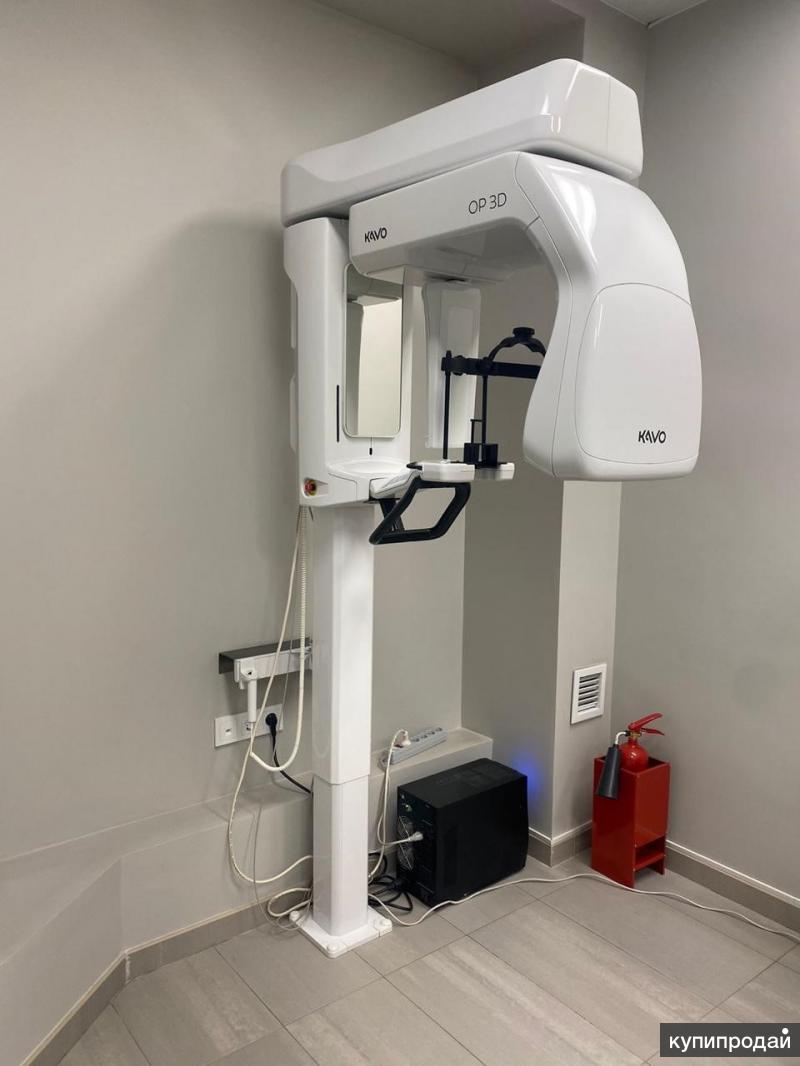

Технологические достижения: Planmeca и ОПТГ